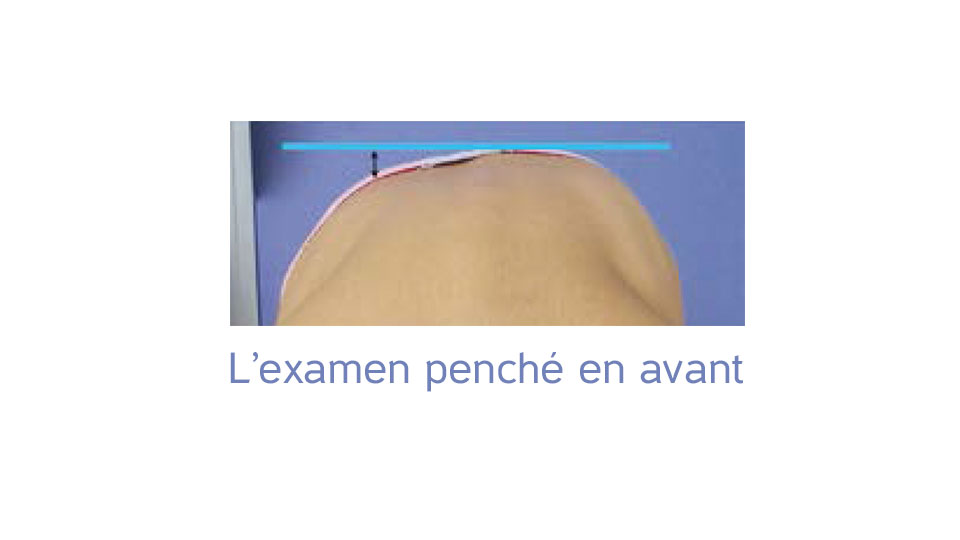

Gibbosité :

bosse produite par une déformation de la colonne vertébrale.